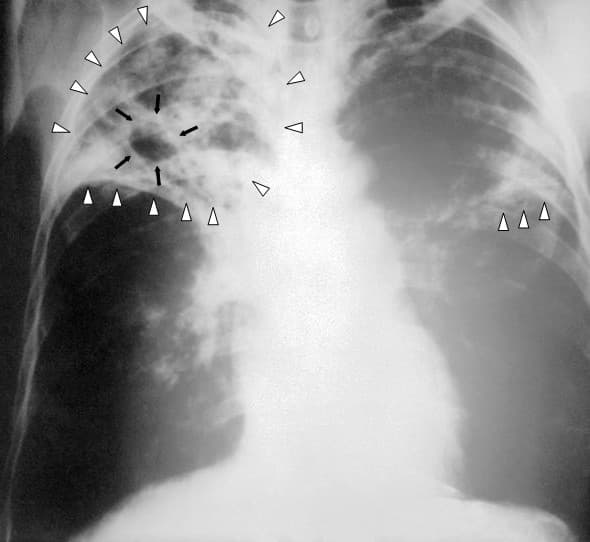

Tuberculosis (TB) is an infectious disease usually caused by Mycobacterium tuberculosis (MTB) bacteria. Tuberculosis generally affects the lungs, but it can also affect other parts of the body. Most infections show no symptoms, in which case it is known as latent tuberculosis. Around 10% of latent infections progress to active disease which, if left untreated, kill about half of those affected. Typical symptoms of active TB are chronic cough with blood-containing mucus, fever, night sweats, and weight loss. It was historically referred to as consumption due to the weight loss associated with the disease. Infection of other organs can cause a wide range of symptoms. Tuberculosis is spread from one person to the next through the air when people who have active TB in their lungs cough, spit, speak, or sneeze. People with latent TB do not spread the disease. Active infection occurs more often in people with HIV/AIDS and in those who smoke. Diagnosis of active TB is based on chest X-rays, as well as microscopic examination and culture of body fluids. Diagnosis of Latent TB relies on the tuberculin skin test (TST) or blood tests. Prevention of TB involves screening those at high risk, early detection and treatment of cases, and vaccination with the bacillus Calmette-Guérin (BCG) vaccine. Those at high risk include household, workplace, and social contacts of people with active TB. Treatment requires the use of multiple antibiotics over a long period of time. Antibiotic resistance is a growing problem, with increasing rates of multiple drug-resistant tuberculosis (MDR-TB). In 2018, one quarter of the world's population was thought to have a latent infection of TB. New infections occur in about 1% of the population each year. In 2020, an estimated 10 million people developed active TB, resulting in 1.5 million deaths, making it the second leading cause of death from an infectious disease after COVID-19.